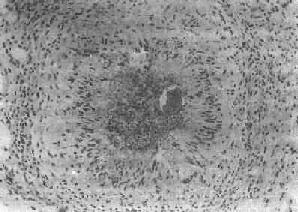

第二节 血吸虫病血吸虫病(schistosomiasis)是由血吸虫寄生于人体引起的地方性寄生虫病。寄生于人体的血吸虫主要有三种:即流行于非洲北部的埃及血吸虫(Schistosoma haematobium);流行于拉丁美洲及非洲中部的曼氏血吸虫(Schistosoma mansoni)以及流行于亚洲的日本血吸虫(Schistosoma japanicum)。在我国因只有日本血吸虫病流行,故通常将日本血吸虫病简称为血吸虫病。 根据1972年在湖南长沙马王堆一号墓出土的西汉女尸及1975年在湖北江陵出土的西汉男尸内皆发现有大量典型血吸虫卵的事实,证明在2100多年前我国已有血吸虫病的流行。本病在我国主要流行于长江流域及其以南的十三个省市的广大水稻作物地区,尤以江苏、浙江、安徽、湖北、湖南、江西等省及上海市效较为严重。过去本病流行猖獗,对广大劳动人民的健康危害极大。新中国成立后,积极发展了防治工作,广东、广西、福建、江苏和上海等五个省市和全国270多个县已基本消灭了血吸虫病。 【病因及感染途径】 日本血吸虫的生活史可分为虫卵、毛蚴、胞蚴、尾蚴、童虫及成虫等阶段。成虫以人体或其他哺乳动物如狗、猫、猪、牛及马等为终宿主,自毛蚴至尾蚴的发育繁殖阶段以钉螺为中间宿主。 血吸虫虫卵随同病人或病畜的粪便排入水中,卵内的毛蚴成熟孵化,破壳而出,以后钻入钉螺体内,经过母胞蚴及子胞蚴阶段后,大量尾蚴发育成熟,并游动于水中。当人畜与疫水接触时,尾蚴借其头腺分泌的溶组织酶作用和其肌肉收缩的机械运动,很快钻入皮肤(或粘膜)并脱去尾部变为童虫。童虫经小静脉或淋巴管进入血液循环,再经右心而到达肺。以后由肺的毛细血管经肺静脉而入大循环向全身散布。只有进入肠系膜静脉的童虫,才能继续发育为成虫,其余多在途中夭折。通常在感染尾蚴后3周左右即可发育为成虫,雌雄成虫交配后即可产卵。虫卵随门静脉血流顺流到肝,或逆流入肠壁而沉着在组织内,约经11天左右逐渐发育为成熟虫卵,内含毛蚴。肠壁内的虫卵可破坏肠粘膜而进入肠腔,并随粪便排出体外,再重演生活周期。虫卵在组织内的寿命约为21天左右。雌雄合抱的成虫在人体内的寿命一般为3~4年。 【病变和发病机制】 血吸虫发育阶段中的尾蚴、童虫及成虫、虫卵等均可引起病变,但以虫卵引起的病变最严重,危害也最大。 1.尾蚴及童虫引起的病变 (1)尾蚴性皮炎:尾蚴侵入皮肤后,可引起皮肤的炎症反应,称为尾蚴性皮炎(cercarial dermatitis)。多发生于重复感染的患者,一般在尾蚴钻入皮肤后数小时至2~3日内发生,表现为红色小丘疹,奇痒,经数日后可自然消退。镜下见真皮充血、出血及水肿,起初有中性及嗜酸性粒细胞浸润,以后主要为密集的单核细胞浸润。 目前认为本病的发病机制主要与迟发性变态反应有关。动物实验证明,转移感染小鼠的淋巴细胞给正常小鼠,再接种尾蚴,经1~2天,局部童虫周围有单核细胞浸润。在反应早期可能有抗体介导的免疫反应参与。 (2)肺部病变:童虫移行到肺时,部分可穿破肺泡壁毛细血管,游出到肺组织中,引起点状出血及白细胞浸润(约在感染后1~2天)并可有血管炎改变,但病变一般轻微而短暂。 童虫经大循环移行到其他器官时也可引起与肺类似的改变。 童虫所引起的各器官点状出血除与童虫的机械作用有关外,还与其代谢产物或虫体死亡后蛋白分解产物所致人体组织的变态反应有关。 宿主感染血吸虫后得到获得性免疫,对再感染产生不同程度的抵抗力。其机制为抗体依赖、细胞介导的细胞毒反应,由IgE或IgG2a抗体,巨噬细胞、嗜酸性粒细胞等参与。主要作用于表面有抗原表达的幼龄童虫,嗜酸性粒细胞有IgG和IgE的Fc受体,当抗体包被童虫后其Fc段与Fc受体结合,并使嗜酸性粒细胞粘附在童虫表面且脱颗粒,释出细胞毒性物质,而起杀伤作用。巨噬细胞也是非常重要的效应细胞。 2.成虫引起的病变 血吸虫在门静脉系统内发育成熟后,其代谢产物可使机体发生贫血、嗜酸性粒细胞增多、脾肿大、静脉内膜炎及静脉周围炎等。在肝、脾的单核吞噬细胞系统的细胞内,常见有黑褐色血吸虫色素沉着,是成虫吞食红细胞后,在虫体内珠蛋白酶作用下,使血红蛋白分解而形成的一种血红素样色素,同样的色素也见于成虫的肠道内。活的成虫本身在静脉内不引起宿主反应,其解释是成虫的表膜内含有宿主的抗原,被宿主认为是“自我”组织而逃避了免疫攻击。成虫死亡后,多在肝内分解,产生毒性,可引起明显的静脉炎和静脉周围炎。死亡虫体周围组织坏死,大量嗜酸性粒细胞浸润,形成嗜酸性脓肿,与血丝虫成虫死亡后引起的变化相似。 3.虫卵引起的变化 虫卵沉着所引起的损害是最主要的病变,虫卵除主要沉着于乙状结肠和直肠壁以及肝外,也常见于回肠末段、阑尾及升结肠等处。肺、脑等其他器官有时也可见到。未成熟的虫卵所引起的病变轻微;含毛蚴的成熟虫卵往往引起虫卵结节形成。按其病变发展过程可分为急性虫卵结节和慢性虫卵结节两种。 (1)急性虫卵结节:肉眼观为灰黄色、粟粒至绿豆大(0.5~4mm)的小结节。镜下见结节中央常有1~2个成熟虫卵,也偶可多达20个以上。这些成熟虫卵的卵壳上附有放射状嗜酸性的棒状体,也称为Hoeppli现象,用免疫荧光法已证实为抗原抗体复合物。虫卵周围是一片无结构的颗粒状坏死物质及大量嗜酸性粒细胞浸润。因其病变类似脓肿,故也称为嗜酸性脓肿(图19-5)。在坏死组织中可混杂多数菱形或多面形屈光性蛋白质晶体,即Charcot-Leyden结晶,系嗜酸性粒细胞的嗜酸性颗粒互相融合而成。随后虫卵周围产生肉芽组织层,其中有以嗜酸性粒细胞为主的炎症细胞浸润,还有单核巨噬细胞、淋巴细胞、浆细胞及少量中性粒细胞。随着病程的发展,肉芽组织层逐渐向虫卵结节中央生长,并出现围绕结节呈放射状排列的类上皮细胞层。类上皮细胞层逐渐加宽,嗜酸性粒细胞显著减少,构成晚期急性虫卵结节(图19-6),这是向慢性虫卵结节发展的过渡阶段。

图19-6 血吸虫病之晚期急性虫卵结节 坏死区及嗜酸性粒细胞浸润范围缩小,其周围出现放射状排列的类上皮细胞层 (2)慢性虫卵结节:急性虫卵结节经10余天后,虫卵内毛蚴死亡,坏死物质逐渐被吸收,虫卵破裂或钙化,其周围除类上皮细胞外,出现异物巨细胞和淋巴细胞,形态上似结核结节,故称为假结核结节(图19-7)。少数虫卵结节一开始即为假结核结节,而不经过急性虫卵结节阶段。最后,假结核结节中的类上皮细胞为纤维母细胞代替,并产生胶原纤维,使结节纤维化。其中央的卵壳碎片及钙化的死卵可长期存留。